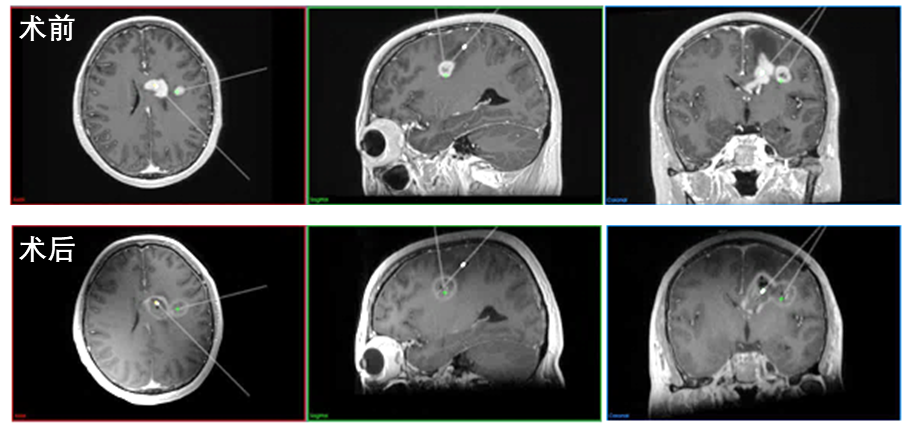

患者为52岁女性,因“头痛伴恶心10余天”入院。根据患者术前影像学及神经系统查体,病变主要位于左额叶内侧,累及胼胝体膝部及侧脑室壁,考虑胶质瘤可能。肿瘤位置深在,多中心且不规则,位于重要功能区,开颅手术切除困难,并发症发生率高。经与患者家属充分沟通、科室讨论后决定采用磁共振引导激光消融术。王宏伟团队首先对患者颅内病变行机器人辅助下立体定向活检,术中快速病理报告提示该病变为胶质瘤伴坏死,随后在机器人导航辅助下,王宏伟团队通过微创切口将两根激光光纤分别精准置入颅内肿瘤靶点。在术中磁共振的实时温度监控下,进行肿瘤精确热凝损毁,利用双波长消融优势,先采用980nm波长激光进行初步消融,迅速形成清晰消融区域,并在此基础上切换为1064nm波长扩大消融区域,随后退针两次,完成不规则病灶中部和尾部的消融;而较小病灶则在1064nm波长激光的热效应作用下实现一次消融。消融后半小时即行术中MRI检查,显示清晰消融边界,基本覆盖原肿瘤强化灶范围。肿瘤消融范围理想,患者术后恢复良好,复查颅脑CT无明显出血,术后6天顺利出院。患者术后病理诊断为胶质母细胞瘤,后续继续进行相关辅助治疗及随访。

MRgLITT手术消融前后患者MRI强化对比